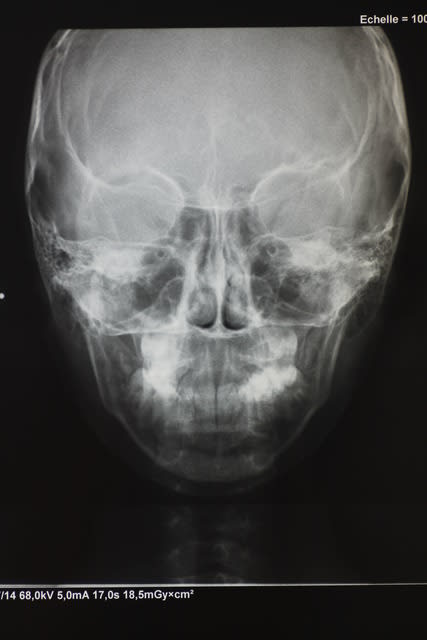

Voici les radios de face et profil.

Analyse de face, j'en ai fait une fois en fac, et c'est tout. Donc, j'en laisse le commentaire à ceux qui en ont l'habitude.

Capucine face vrac9k - Eugenol

regarde sur la radio de face s'il y a un problème basal transversal ou s'il y a linguoversion alvéolaire

De profil tu veux dire. Et de face tu verras si tu a vraiment un déficit transversal basal.

On verra s'il y a un déficit transversal basal sur la télé de face.